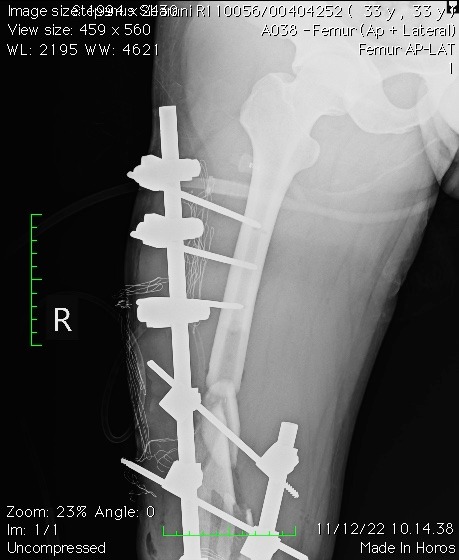

Teks poto : Korban kecelakaan yang terjadi di Pekanbaru Riau 10 Desember 2022,Stepanus Sibarani salah satu karyawan toko ditabrak oleh mobil tronton.

PEKANBARU, Satuju.com - Korban kecelakaan yang terjadi di Pekanbaru Riau 10 Desember 2022 lalu benar-benar tragis dan apes bagi Stepanus Sibarani salah satu karyawan toko ditabrak oleh mobil tronton hingga tangan dan kaki hancur dan patah di beberapa bagian. Bahkan menurut informasi yang diterima tim media dari pihak keluarga korban, didampingi kuasa hukumnya Asteriaman Nazara, SH menjelaskan kejadian yang dialami kliennya tersebut janggal dan memprihatinkan. Sabtu (28/1/2023).

Ket. Poto : Hasil rontgen (11/12/2022) 10.14.38